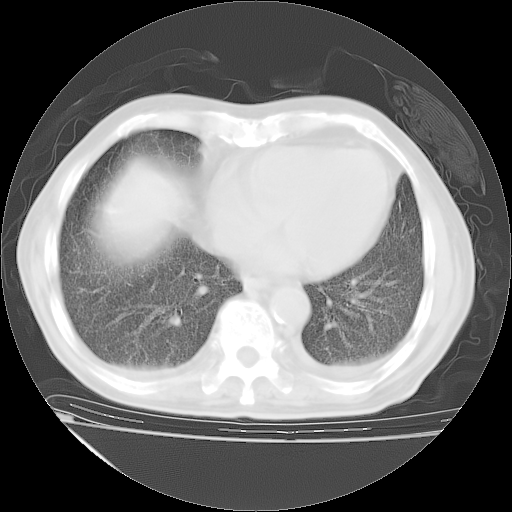

甲强龙80mg/日+抗结核治疗(异烟肼+利福霉素+乙胺丁醇)10天。复查肺部CT。

治疗10天肺部CT